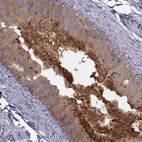

Immunohistochemistry analysis in human epididymis and endometrium tissues using HPA028445 antibody. Corresponding CRISP1 RNA-seq data are presented for the same tissues.